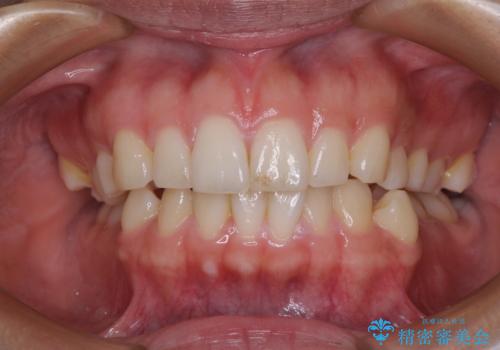

【モニター】突出した前歯 補助装置を併用したインビザライン矯正

- 上下前歯が非接触となり、前方に突出していることを気にして来院された患者様です。

咬合力が強く、全体的に歯がすり減っているため、インビザライン単独での上顎歯列移動は困難と判断し、補助装置により上顎歯列を後方移動させ、その後インビザラインにて仕上げていくこととしました。

補助装置なしでも改善できる可能性はありましたが、補助装置で確実性を上げ、短期間できっちりと仕上げることができました。